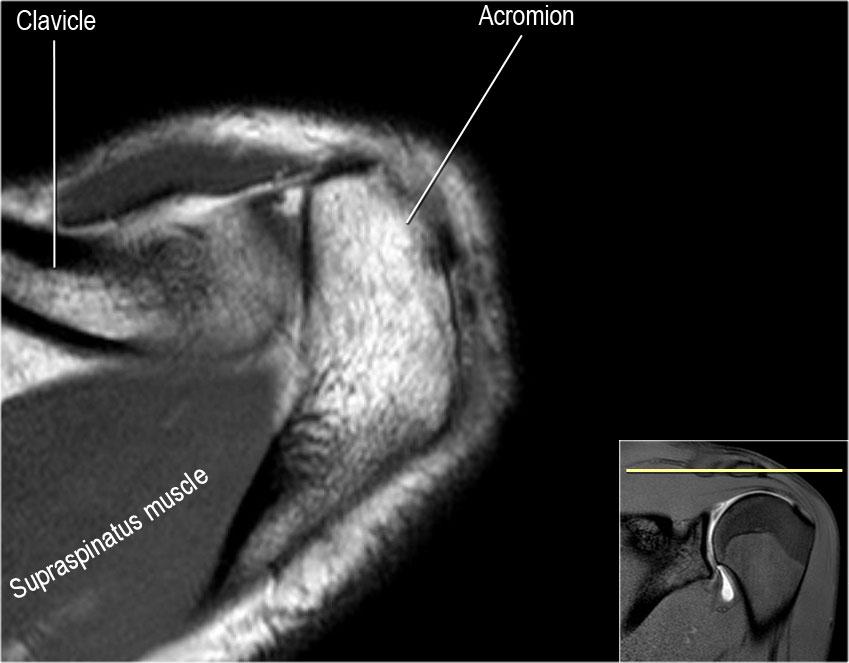

Trục của gân cơ trên gai

Gân cơ trên gai là cấu trúc quan trọng nhất của chóp xoay và là vị trí thường gặp của bệnh lý gân và rách gân.

Rách gân cơ trên gai được quan sát rõ nhất trên các chuỗi chụp nghiêng vành và chuỗi ABER.

Trong nhiều trường hợp, trục của gân cơ trên gai (đầu mũi tên) xoay ra trước nhiều hơn so với trục của cơ (mũi tên vàng).

Khi lập kế hoạch chuỗi chụp nghiêng vành, tốt nhất nên tập trung vào trục của gân cơ trên gai.